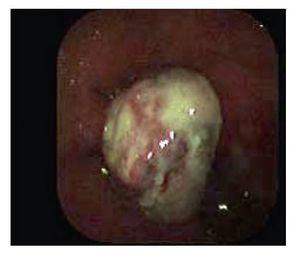

Paciente masculino de 78 años de edad sin antecedentes de importancia que refiere padecimiento de 3 meses de evolución con sensación de masa anal, que refiere prolapso al momento de la defecación. A la exploración se encuentra región perianal normal, no evidencia de lesiones, al realizar tacto rectal se palpa lesión de aproximadamente 2 cm de diámetro que se encuentra en el conducto anal y se evidencia al hacer anoscopia, la lesión protruye al momento de realizar maniobra de Valsalva (Foto 1), motivo por el cual se decide llevar a cabo rectosigmoidoscopia para evaluar la lesión y toma de biopsias (Foto 2) reportándose hallazgos histológicos con relación a melanoma maligno, se inicia estudio de extensión con TAC y radiografía de tórax libres de enfermedad metastásica. En decisión conjunta con los familiares y el deseo del paciente al no contar con un estoma definitivo, se decide hacer resección amplia de la lesión con adecuada evolución del paciente y control de los síntomas. En el estudio histopatológico de la pieza se corroboró el diagnóstico de melanoma anal, reportándose bordes quirúrgicos libres. Hasta su cita de control a la consulta 8 meses posteriores a la cirugía el paciente continúa libre de enfermedad.

Foto 2. Melanoma de conducto anal. Imagen endoscópica.